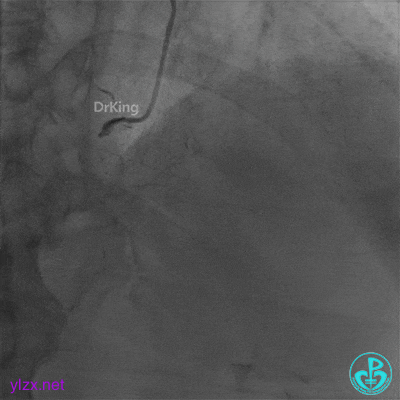

并反复经刺破球囊冠脉内静推硝普钠5次(100μg/次),右冠脉血流恢复TIMI 3级,右冠脉近端可见夹层。

支架近端植入3.5×13mm支架覆盖夹层。

最后结果示右冠脉近端支架外仍然可见夹层。